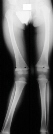

knee(image1). At a four month follow up now 13 months after injury a progression

to 27 degrees was noted(image2). Neutral alignment of the left knee was

noted.